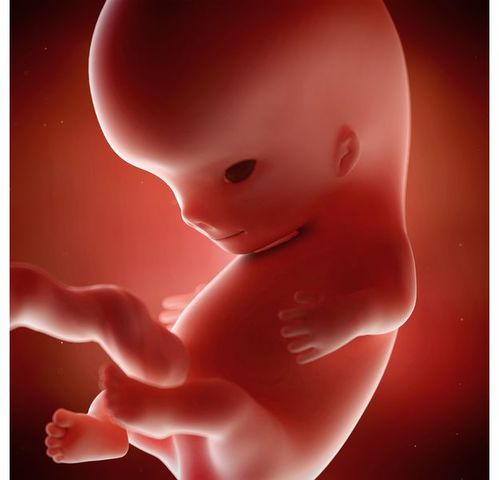

• Desarrollo fetal

Esta etapa comienza desde el momento en que se ha completado la etapa embrionaria, y hasta que se produzca el parto. Durante la vida fetal no se forman órganos o tejidos nuevos, sino que se produce la maduración de los ya existentes. Al finalizar la décima semana de edad gestacional el embrión ha adquirido su forma básica y el siguiente período es el del desarrollo fetal, cuando los órganos se desarrollan completamente

• Semanas 9 a 12

Semanas 9 a 12

Los párpados se cierran y no se vuelven a abrir casi hasta la semana 28

La cara está bien formada

Las extremidades son largas y delgadas

Los genitales aparecen bien diferenciados

Los glóbulos rojos se producen en el hígado

El tamaño de la cabeza corresponde casi a la mitad del tamaño del feto

El feto puede empuñar los dedos

Aparecen los brotes dentarios